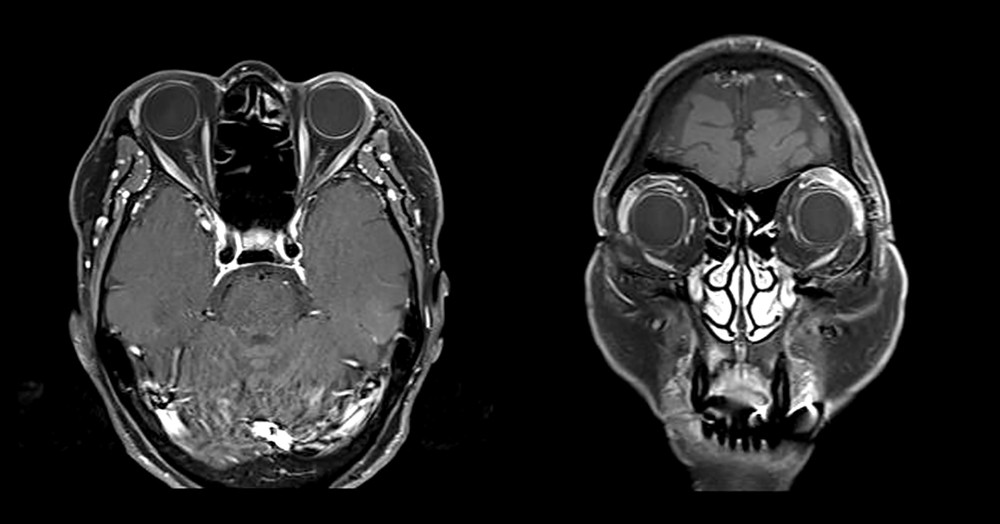

Figure 1 from Kimura disease case report and brief review of Kimura Disease Case Report And Brief Review Of Literature kimura disease (kd) is a benign chronic inflammatory disorder attributed to an immune mediated hypersensitivity. kimura disease is an extremely rare, chronic inflammatory disorder in which lymphoid and vascular. kimura disease is a benign immune mediated chronic inflammatory disorder presents with tumor like. kimura disease is a rare chronic inflammatory disorder of unknown cause, primarily seen. Kimura Disease Case Report And Brief Review Of Literature.